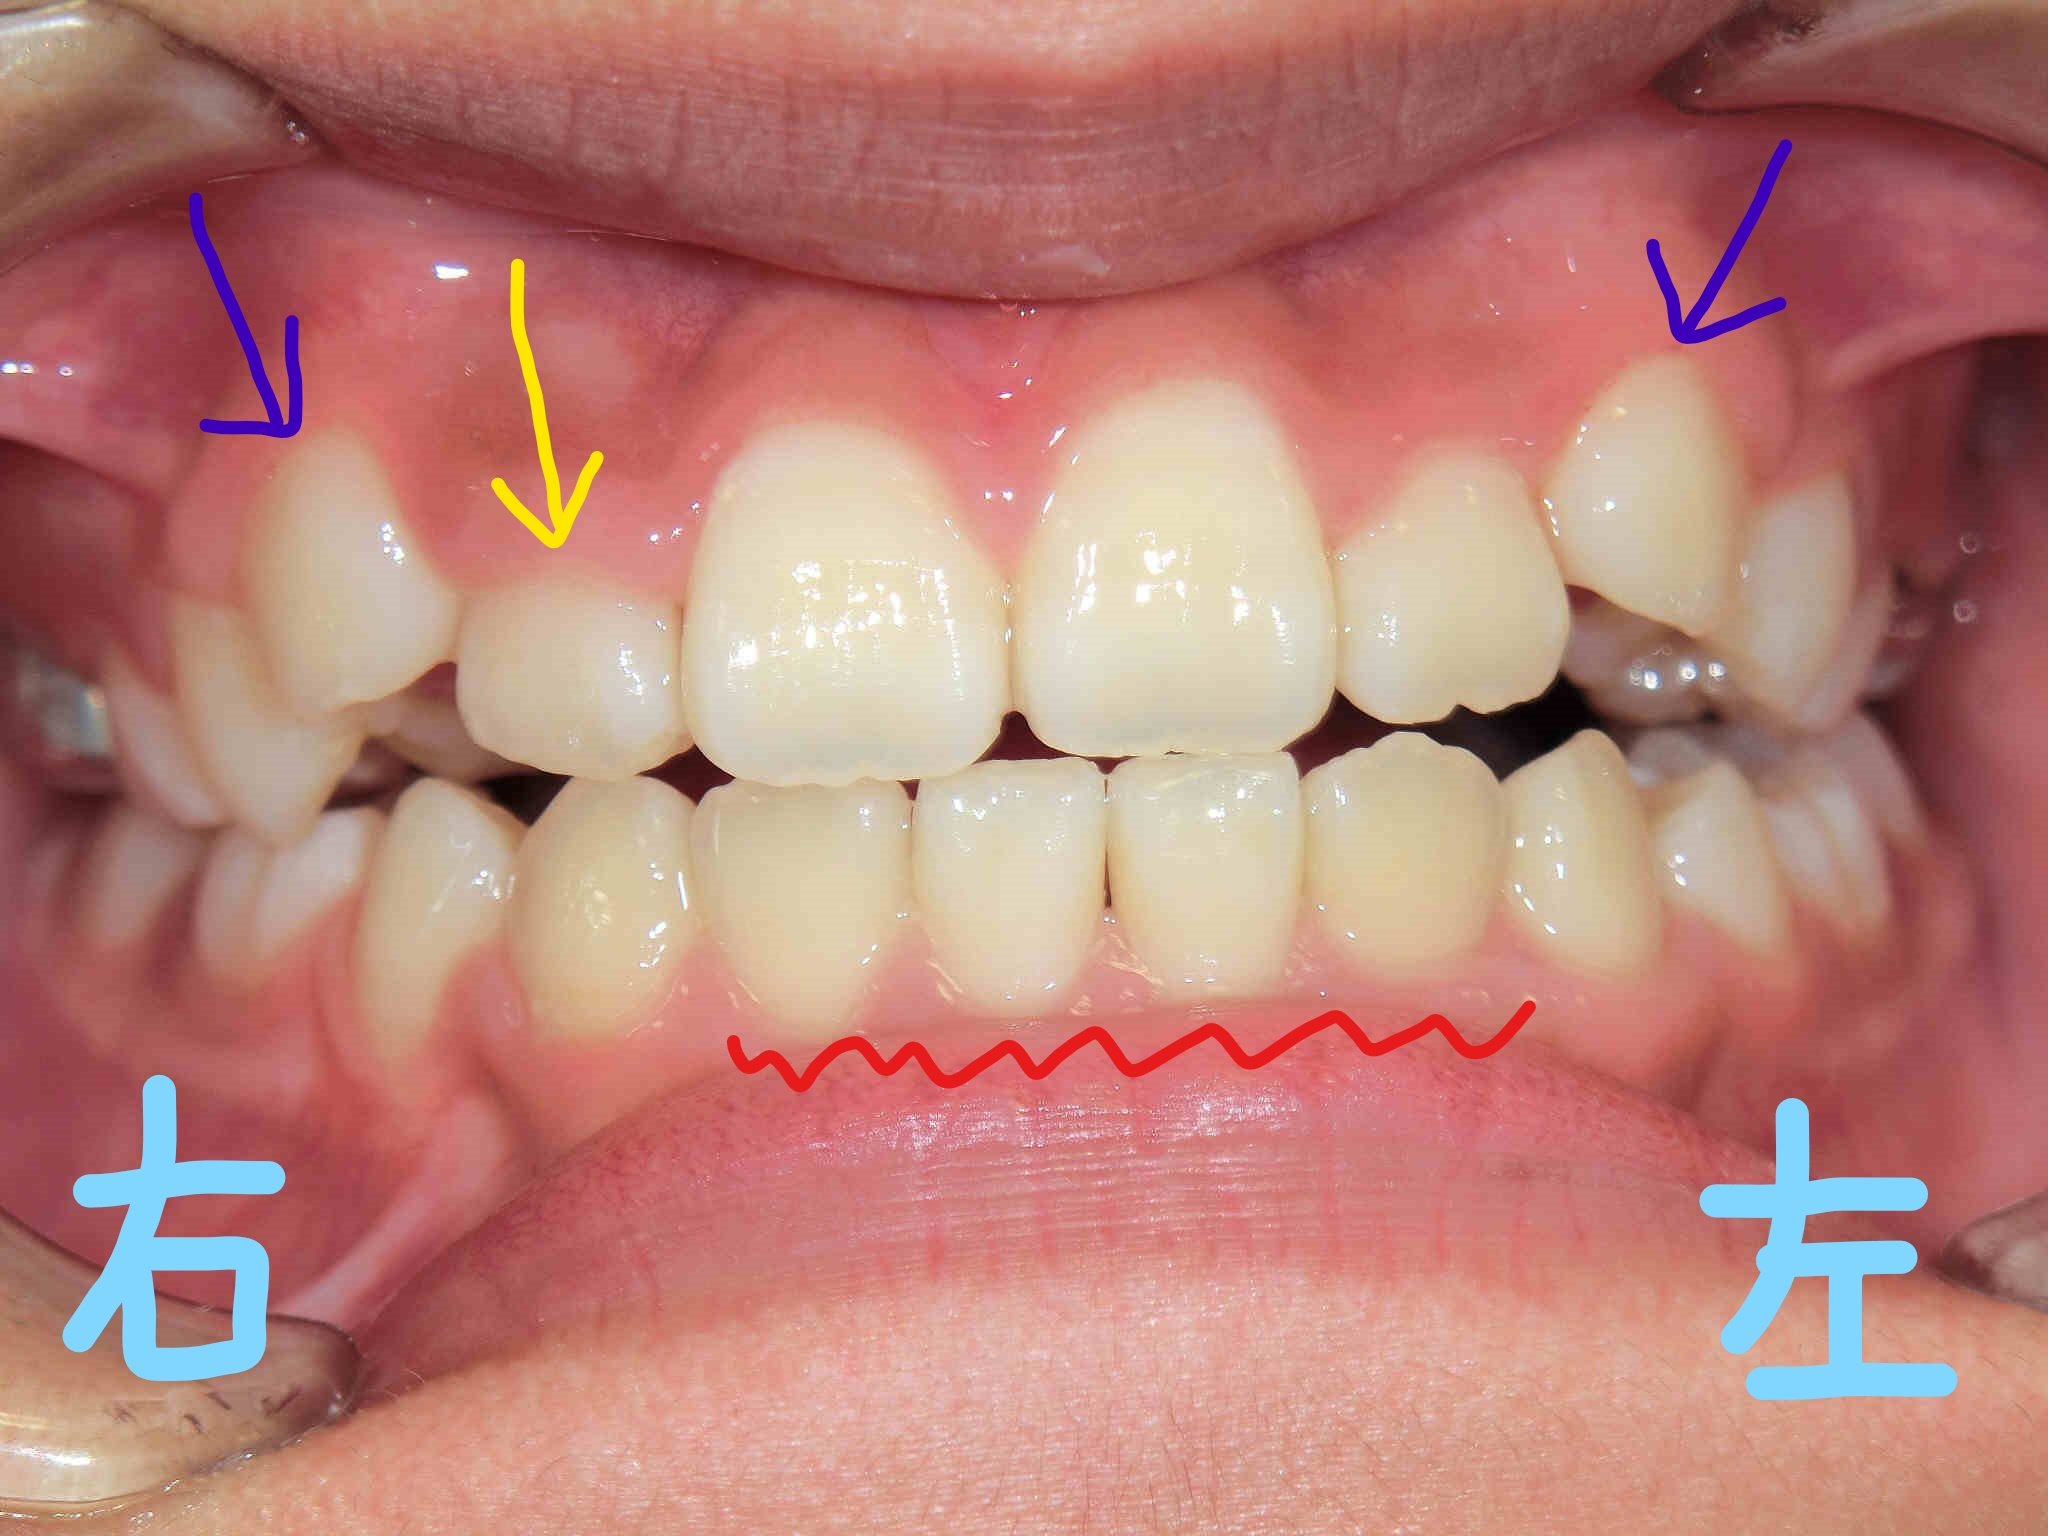

左上は正面からの口腔内写真、右上は下から見上げた正面の写真です。下顎前歯(赤色波線部)の叢生(いわゆるガタガタの歯並び)は改善が見られ、歯列が整ってきています。

一方で、上顎歯列の拡大により右上前歯(黄色矢印)は前方へ誘導され、良好な方向へ変化しつつありますが、両側の上顎犬歯(紫色矢印)が歯列の外側に位置しているため、歯列内に誘導するにはさらなるスペースの確保が必要と判断しました。そのため、上顎に固定式の拡大装置(急速拡大装置〈RPE〉)を使用する方針といたしました。

次回は、固定式の拡大装置を装着してから3か月後の状態をご紹介いたします。